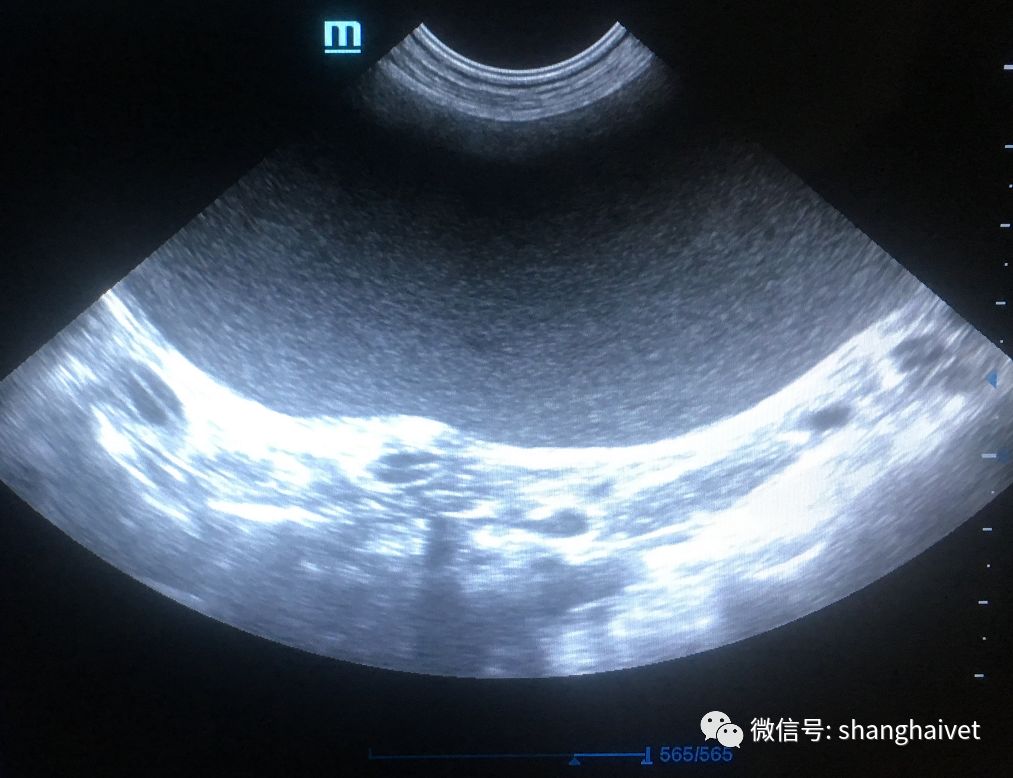

▲腹部B超扫描结果

B超提示两侧子宫角直径增粗回声中等不均质,果不其然,是子宫蓄脓(子宫的感染)。主人对这个结果甚为诧异,平时养护颇注意卫生,也没有进行过交配,为什么还会感染呢?